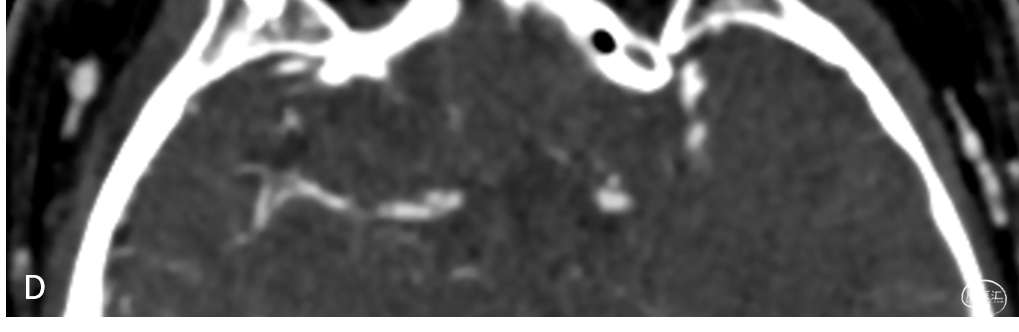

头颅CTA提示:右侧大脑中动脉M1段闭塞;左侧椎动脉V4段重度狭窄(C、D)

头颅CTP:右侧大脑中动脉区域明显低灌。